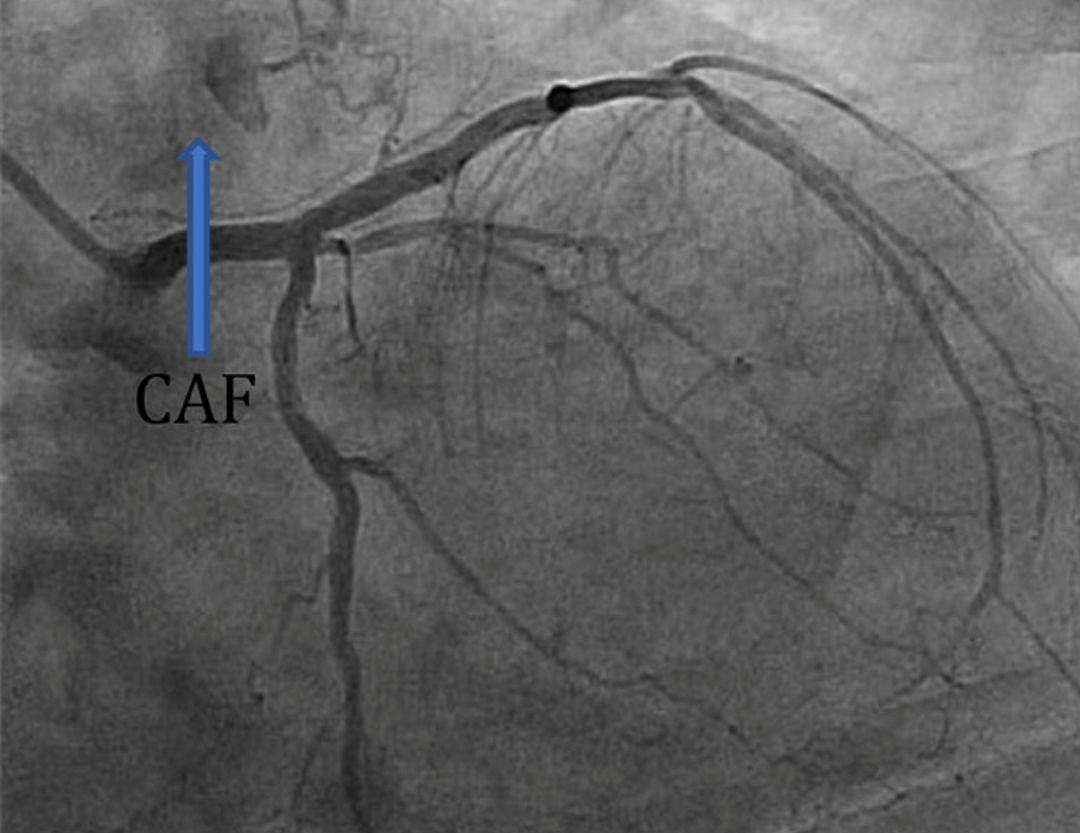

在进行冠脉造影时,有时可以见到下面这些图像。

图2 右冠脉-右心房CAF

与冠心病一样,冠脉造影是诊断CAF的金标准。造影显示解剖结构较清晰,对小CAF显示较好,同时也可以评估CAF对血流的影响。但是对结构复杂的CAF,造影颇为吃力,有报道称造影对复杂CAF结构的诊断正确率仅为35%-50%,这时需要CT等其他影像手段协助。